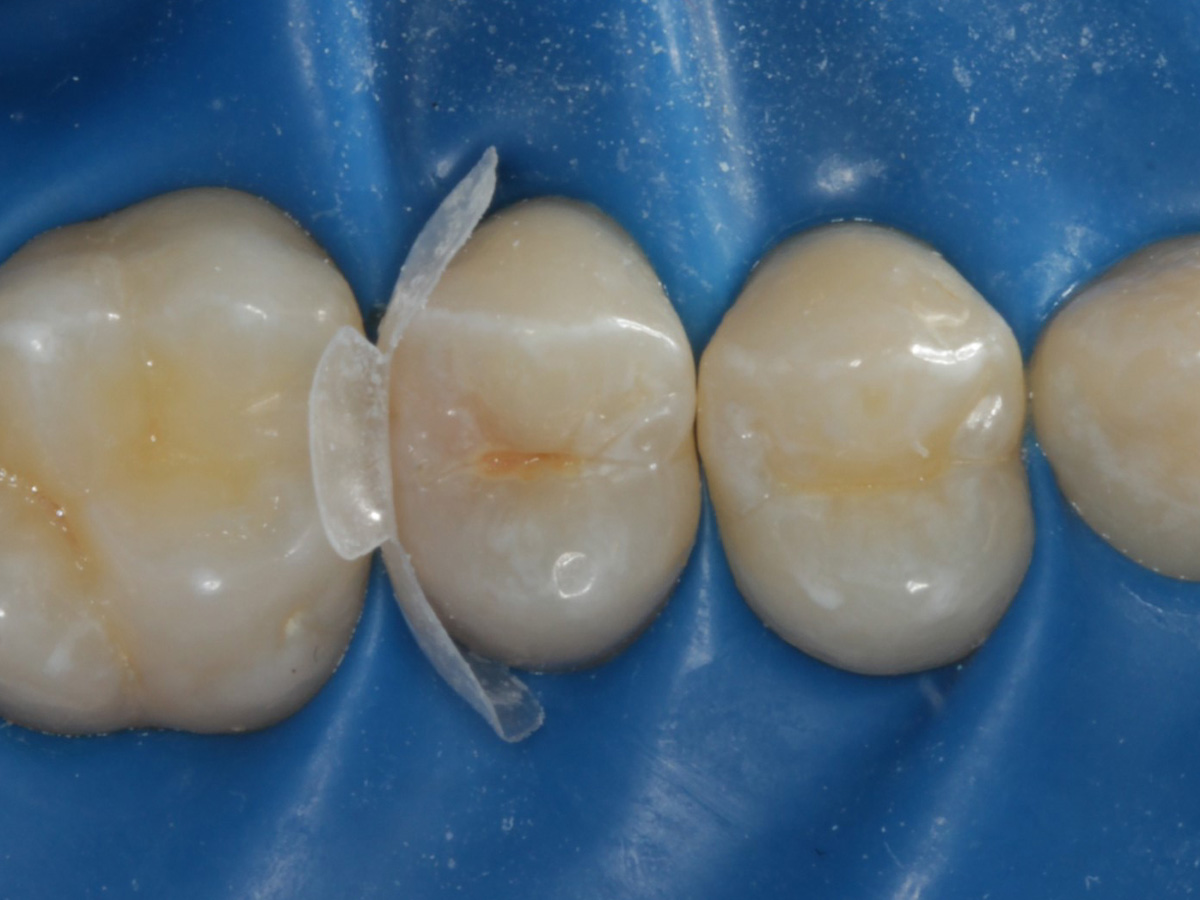

Abbildung 4

Schutz des Nachbarzahnes und des Kofferdams mit wiederverwandter Bioclear Biofit Matrize (gereinigt und sterilisiert)